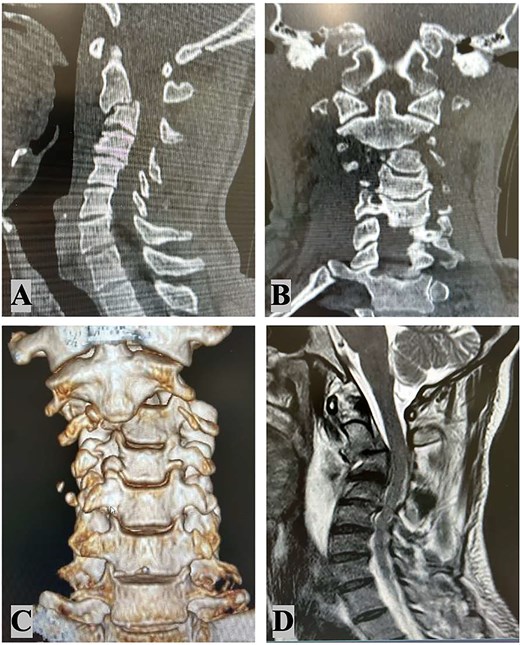

A 48-year-old male with no prior comorbidities was involved in a motorcycle accident, colliding with a car at ~50 mph. He was admitted to the emergency department with a Glasgow Coma Scale score of 14, muscle weakness in all four limbs (grade IV), and severe cervical pain [Visual Analog Scale (VAS) 9]. Initial clinical assessment suggested a significant cervical spine injury with neurological involvement. Radiological evaluation included magnetic resonance imaging (MRI), computed tomography (CT) scan (Fig. 1) and angiography (Fig. 2). MRI revealed a C2–C3 subluxation with right lateral listhesis, where the C2 body was positioned on the right lateral aspect of C3, with locked facets on the left. A fracture line was identified through the C3 body at the right pedicle junction, with splayed bone fragments and slight axial rotation. Sagittal imaging showed anterior listhesis of C2 over C3, loss of cervical lordosis, and segmental kyphosis, with an intact ligamentum flavum and no disc herniation at C2–C3. Angiography confirmed total occlusion of the left vertebral artery and dissection of the right internal carotid artery. The injury was classified as AO C-N3-M4 and Levine Edwards Type III, indicating severe angulation and displacement with facet dislocation.

Radiological findings: Cervical spine sagittal computed tomography scan (A); cervical spine coronal CT scan (B) 3D coronal CT scan (C); MRI – C2–C3 subluxation with right lateral listhesis, where the C2 body was positioned on the right lateral aspect of C3 (D).